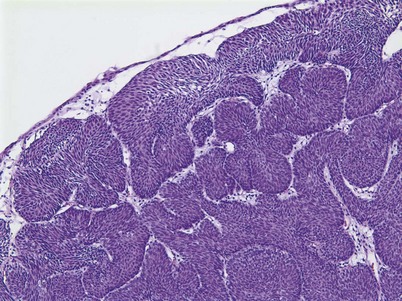

An inverted papilloma is a benign proliferative lesion that is associated with chronic inflammation or bladder outlet obstruction and can be located throughout the bladder but most commonly on the trigone, comprising less than 1% of all bladder tumors (Sung et al, 2006; Jones et al, 2007; Kilciler et al, 2008). Inverted papillomas demonstrate an inverted growth pattern composed of anastomosing islands of histologically and cytologically normal urothelial cells invaginating from the surface urothelium into the lamina propria but not into the muscularis propria (Fig. 80–1) (Sung et al, 2006). When diagnosed according to strictly defined criteria (e.g., lack of cytologic atypia), inverted papillomas behave in a benign fashion with only a 1% incidence of tumor recurrence (Sung et al, 2006; Kilciler et al, 2008). Occasionally, inverted papillomas are present with coexistent urothelial cancer elsewhere in the urinary system, occurring more commonly in the upper tract than the bladder (Asano et al, 2003). The use of fluorescent in-situ hybridization (FISH) to evaluate chromosomal changes can distinguish between an inverted papilloma and a urothelial cancer with an inverted growth pattern (Jones et al, 2007). Transurethral resection is the treatment of choice.